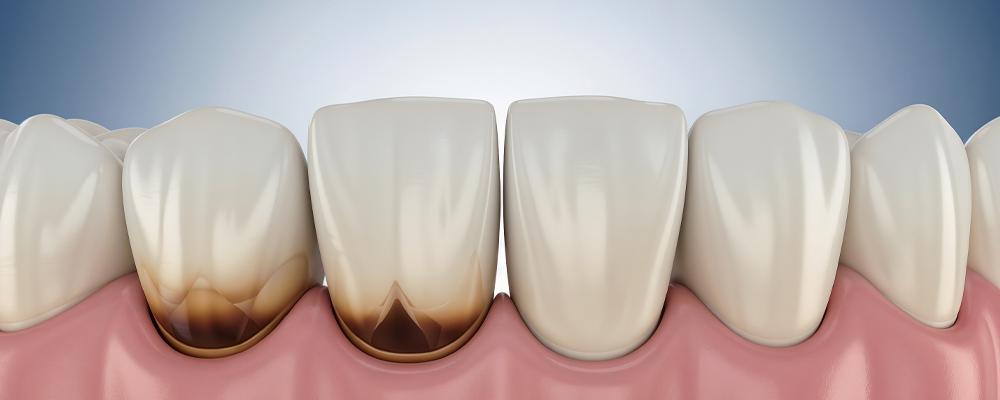

「根面う蝕」は加齢などの影響で歯ぐきが下がり、歯の根の部分(根面)が露出したところにできる虫歯です。通常の虫歯はエナメル質から始まりますが、根面う蝕はエナメル質が存在しない部位に起こります。特に歯の根元は酸に対する抵抗力が弱いため非常に虫歯になりやすく、進行も早いため、歯を失うリスクが高い虫歯です。

- 歯ぐきが下がって歯の根の部分が露出したところにできる

- 歯の根元は酸に弱く虫歯になりやすい

- 気づきにくく進行しやすい

痛みが少なく気付きにくい虫歯のため要注意

根面う蝕は、黒っぽく変色していても痛みが少ないことが多いです。そのため、「知覚過敏かな」と思って放置されることもあります。しかし放置すると、歯の神経まで進行し、最終的には抜歯が必要になることもあります。大人の歯は一度失うと戻りません。だからこそ、早期発見と予防が重要なのです。